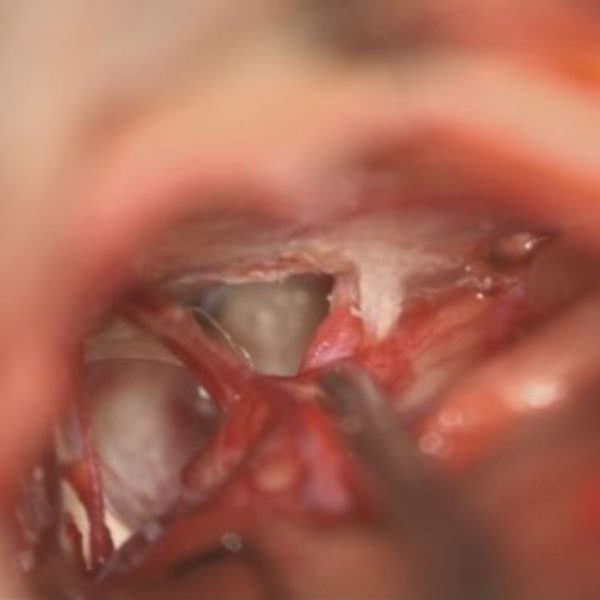

症例 '26年4月

No.

589

病名

'26年4月

70代

左三叉神経痛

減圧後